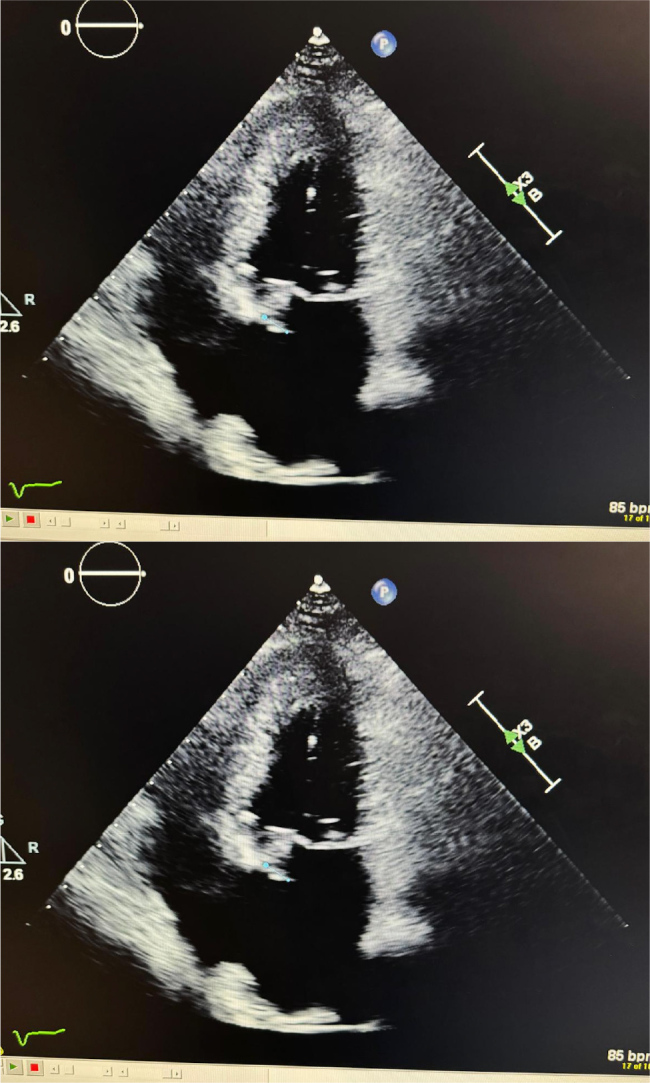

Case description: A 73-year-old woman with coronary artery disease, atrial fibrillation, repaired mitral valve prolapse and on warfarin presented with sudden left lower quadrant abdominal pain. She was hypotensive (BP 60/45 mmHg) and exhibited periumbilical tenderness. Laboratory findings included white blood cell count 18,000 cells/μl, haemoglobin 7.7 g/dl, platelets 1,023,000/μl, aspartate transferase 509 U/l, alanine transaminase 313 U/l and positive SARS-CoV-2. Non-contrast CT of the abdomen/pelvis revealed haemoperitoneum, rectus sheath haematoma and a hypodense hepatic lesion. Contrast-enhanced CT confirmed a left hepatic lobe pseudoaneurysm, supported by Doppler ultrasound. Coil embolisation of the pseudoaneurysm stabilised the patient's haemodynamics. Blood cultures grew Staphylococcus epidermidis, prompting treatment with meropenem and vancomycin due to her prosthetic mitral valve. Transthoracic echocardiogram showed valve vegetation, though a transoesophageal echocardiogram later revealed no vegetations. Follow-up imaging showed a stable thrombosed pseudoaneurysm. The patient remained stable and was transferred for mitral valve replacement. Blood cultures remained negative, but antibiotics were continued for six weeks. Warfarin was resumed without further bleeding.